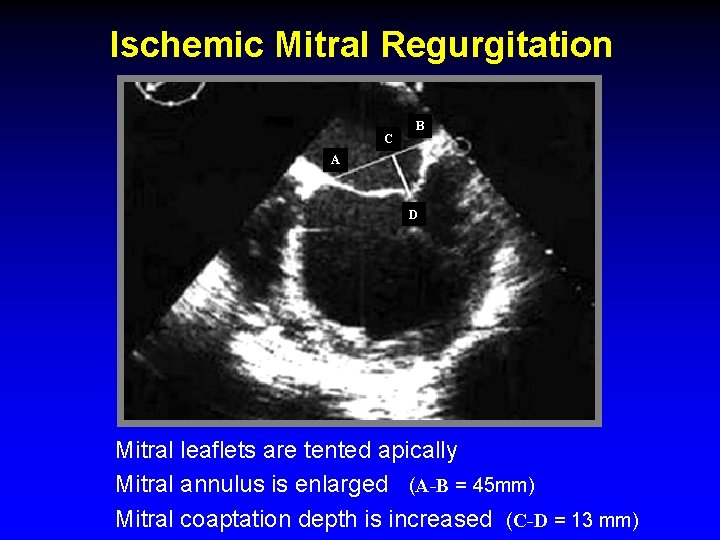

Ischemic Mitral Regurgitation C B A D Mitral leaflets are tented apically Mitral annulus is enlarged (A-B = 45 mm) Mitral coaptation depth is increased (C-D = 13 mm)